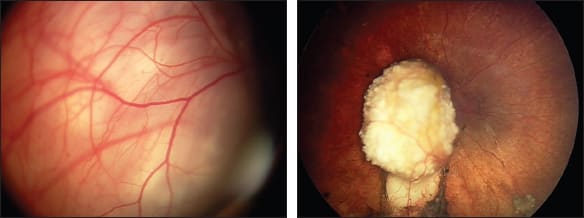

Figure 1. Dramatic reduction and complete calcification of advanced retinoblastoma (left, before; right, after) treated with OAC alone.

As we have learned, the procedure is more like surgery, in that it requires careful screening of appropriate candidates, assembling a team of anesthesiologists, nurses, technicians, pharmacologists, and pediatric oncologists, acquiring sophisticated equipment, modifying what was planned, and dealing with unexpected consequences. Thus, we now prefer the term “ophthalmic artery chemosurgery” (OAC) (Figure 1).